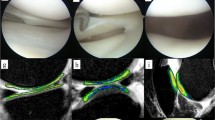

μCT evaluation of subchondral bone and cartilage at the medial tibial plateau

Although the subchondral bone volume was larger in the MMT rats than in the sham controls in all 3 zones, the most significant difference was measured in Zones 1 and 2. There was no difference in BMD between the sham and MMT rats. Cartilage volume was greater in Zones 1 and 3 but was significantly less in Zone 2 in the MMT rats, compared to the sham controls. Cartilage thickness was greater in Zone 1 but was significantly less in Zone 2 (p < 0.001) in the MMT rats, compared to the sham controls. Cartilage thickness in Zone 3 was somewhat higher in sham rats relative to MMT rats (Table 3; Fig. 3).

2D (a, b) µCT images of the tibial epiphysis from a sham rat (A) and MMT rat (B). Doted squares indicate area of subchondral bone used for zonal analysis. 3D images of subchondral bone are depicted for sham (Aa) and MMT rat (Bb). Arrow indicates thicker subchondral bone in MMT rat. C (sham) and D (MMT) shows a contrast µCT image of the proximal tibial epiphysis of the same rats shown in A and B. The length of the medial tibial plateau was measured for each sample and was then divided into three zones ranging from 0.8 to 1.0 mm in length. Zone 1 (z1) was placed on the outside of the medial edge of the joint, and Zone 3 (z3) was placed on the inside of the tibial plateau, adjacent to the central collateral ligaments as exemplified in C. Zones are delineated by dotted lines. Cc (sham) and Dd (MMT) show color thickness (“heat”) maps of the articular cartilage at the medial tibial plateau. Arrow indicates a lack of viable cartilage that covers the medial tibial plateau in MMT rat

Histology

Histological evaluation of articular cartilage revealed classic images of cartilage degradation caused by the MMT surgery: thinning to complete absence of the cartilage due to chondrocyte death or atrophy, cartilage fibrillation and the presence of osteophytes. In the control rats, the articular cartilage at the medial tibial plateau grew progressively thicker from the most medial (Z1) to the most lateral part (Z3), as depicted on by morphometry on histological sections (Table 4; Fig. 4). MMT surgery triggered thickening of the cartilage in the most medial half of Zone 1 next to the osteophytes. The cartilage was thin and occasionally completely missing in Zone 2 in the MMT rats. Cartilage thickness in Zone 3 in MMT rats was decreased relative to sham controls, but the change was not as drastic as in the Zones 1 and 3 (Table 4; Fig. 4). Damage score, Cartilage matrix loss width for 0, 50 and 100 %, Total cartilage degeneration width and Significant cartilage degeneration width were all significantly (p < 0.001) elevated in MMT rats compared to sham controls (Table 4).

It was previously demonstrated that EPIC μCT imaging provided a reproducible method to assess 3-D distribution of glycosaminoglycans (GAGs) in the articular cartilage of laboratory rats [23, 49], and that imaging data strongly correlated with histological findings [21–23]. Three-dimensional images could be used to guide the histological evaluation of articular cartilage by indicating areas of cartilage damage so that areas warrant evaluation will not be missed on histological sections. Three-dimensional cartilage analyses by μCT unequivocally demonstrated the extent of cartilage damage following MMT surgery and micro-anatomical localization of the damage (Z1 and Z2), as well as adaptation and thickening of the articular cartilage at the most medial corner of Zone 1, bordering the region of osteophyte formation. Imaging data of the articular cartilage were correlated well with traditional histological methods, as well as with serum biomarkers of cartilage degradation (CTX-II). Serum biomarkers of bone metabolism reflect the change in bone formation and bone resorption in the entire skeleton. We hypothesize that the magnitude of bone remodeling at the metaphyseal and subchondral bone (including ostephytes) was probably too small to be picked in the serum at the end of 10-week study. Also, serum biomarkers reflect only bone resorption and formation at the time of serum collection and this is probably another reason why these biomarkers have only limited diagnostic and prognostic value in OA patients [19, 50].